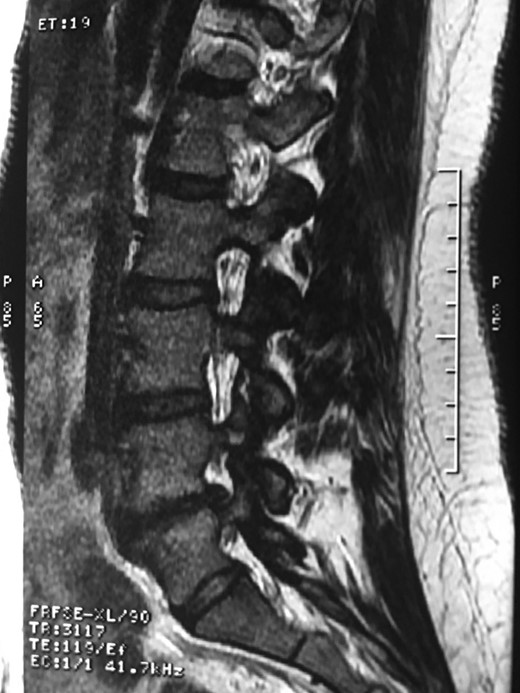

A 42-year-old female presented to the clinic with a history of chronic low back pain. She reported no relevant medical history. She had already been treated in the last 4 years by general practitioners with analgesics and home based physiotherapy with no satisfactory results. She had two previous admissions to the emergency department where morphine was prescribed to control the pain on her lower back. She was under ambulatory treatment with diclofenac, and tizanidine with partial relief of symptoms. Her main complaint was pain on the lower lumbar back with no radiation to the lower extremities. In her physical evaluation she presented limitation to full rotation and bending of the lumbar spine due to pain. Lasegue sign was negative, sensitivity, reflexes, sagittal balance, distal muscular strength and pulses were normal. Radiographs showed an overdeveloped left transverse process of the fifth lumbar vertebra which contacts with the sacrum at the left sacral wing with signs of degeneration at the same site (Fig. 1). Magnetic resonance imaging (MRI) studies were obtained (Figs 2–5). The patient was taken to the operating room where infiltration with 1 mL of lidocaine and 40 mg of Triamcinolone was performed in the pseudoarticulation between the left transverse process and the sacrum under fluoroscopic guidance. She reported a complete relief of pain after the procedure. At three months follow-up she was managed with strengthening and stabilizing exercises for the lumbar spine and postural education was initiated. She remains asymptomatic at her 12 months follow up.

RMN of the patient showing smaller facets in the anomalous articulation and healthy disc compared to the supradjacent one (next figure).

Degenerative changes at the facets and disc in the adjacent segment.

The partial fusion at the lower part of the lumbosacral transition produces important alterations in normal biomechanics at the levels immediately above and below the LSTV. Changes such as hypermobility and abnormal torque moments are present at the level above the LSTV, predisposing it to early degeneration (early disc pathology and facet joint degenerative disease). Restricted movement below the LSTV produces a protective effect against degeneration of disc and facets and is related to changes (facets are smaller and coronally oriented) in the dimensions of the lower level facet joints [7]. These alterations can be verified in the adjacent levels of the LSTV in our patient.